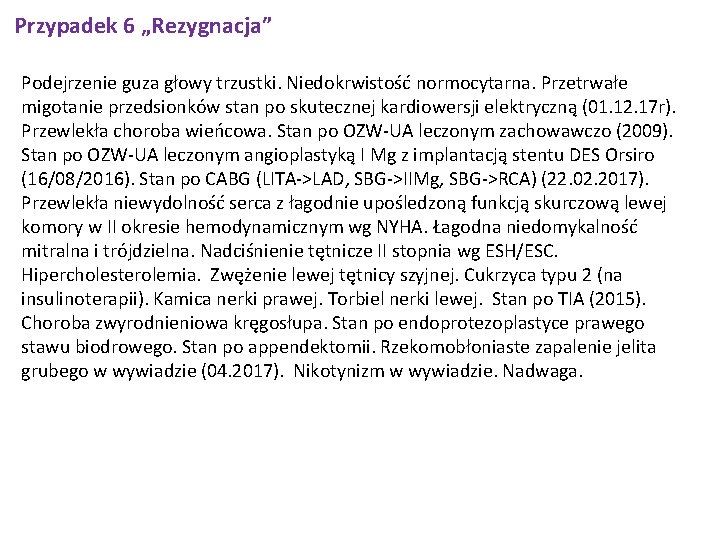

Przypadek 6 „Rezygnacja” Podejrzenie guza głowy trzustki. Niedokrwistość normocytarna. Przetrwałe migotanie przedsionków stan po skutecznej kardiowersji elektryczną (01. 12. 17 r). Przewlekła choroba wieńcowa. Stan po OZW-UA leczonym zachowawczo (2009). Stan po OZW-UA leczonym angioplastyką I Mg z implantacją stentu DES Orsiro (16/08/2016). Stan po CABG (LITA->LAD, SBG->IIMg, SBG->RCA) (22. 02. 2017). Przewlekła niewydolność serca z łagodnie upośledzoną funkcją skurczową lewej komory w II okresie hemodynamicznym wg NYHA. Łagodna niedomykalność mitralna i trójdzielna. Nadciśnienie tętnicze II stopnia wg ESH/ESC. Hipercholesterolemia. Zwężenie lewej tętnicy szyjnej. Cukrzyca typu 2 (na insulinoterapii). Kamica nerki prawej. Torbiel nerki lewej. Stan po TIA (2015). Choroba zwyrodnieniowa kręgosłupa. Stan po endoprotezoplastyce prawego stawu biodrowego. Stan po appendektomii. Rzekomobłoniaste zapalenie jelita grubego w wywiadzie (04. 2017). Nikotynizm w wywiadzie. Nadwaga.